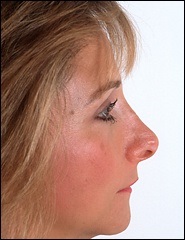

A fénykép a bal oldalon mutatja egy ember tipikus megnövekedett nazális gerinc. Ez jelentősen növeli az orrát előre. A fénykép után a művelet ugyanaz az ember nagyon jól néz ki.

A nő látható a felső fotó túl kiálló orrát. Ezt segíti elő a túlzott acanthion. Ezen kívül volt egy jelentősen nőtt a felső ajak. Amint azt a jogot, fotó, rövidítést követően az orrhegy és változtatni az alakját a felső ajak volt a hatása lerövidíti az orrát. Meg kell jegyezni, hogy ebben az esetben a hosszúkás gerinc nem vezet túlzott nyitó columella.